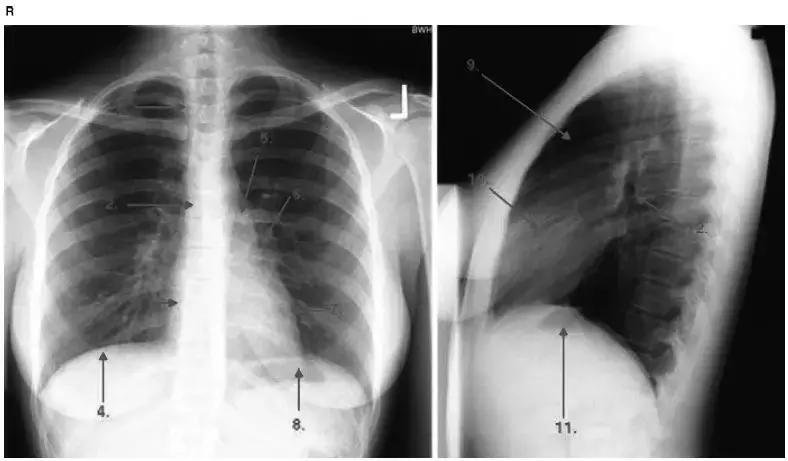

图4-1 正常的胸片

1.气管;2.气管隆嵴;3.右心房;4.右侧膈肌;5.主动脉结;6.左肺门;7.左心室;8.左侧膈肌(胃泡);9.胸骨后透亮区;10.右心室;11.左侧膈肌(胃泡);12.左上叶支气管